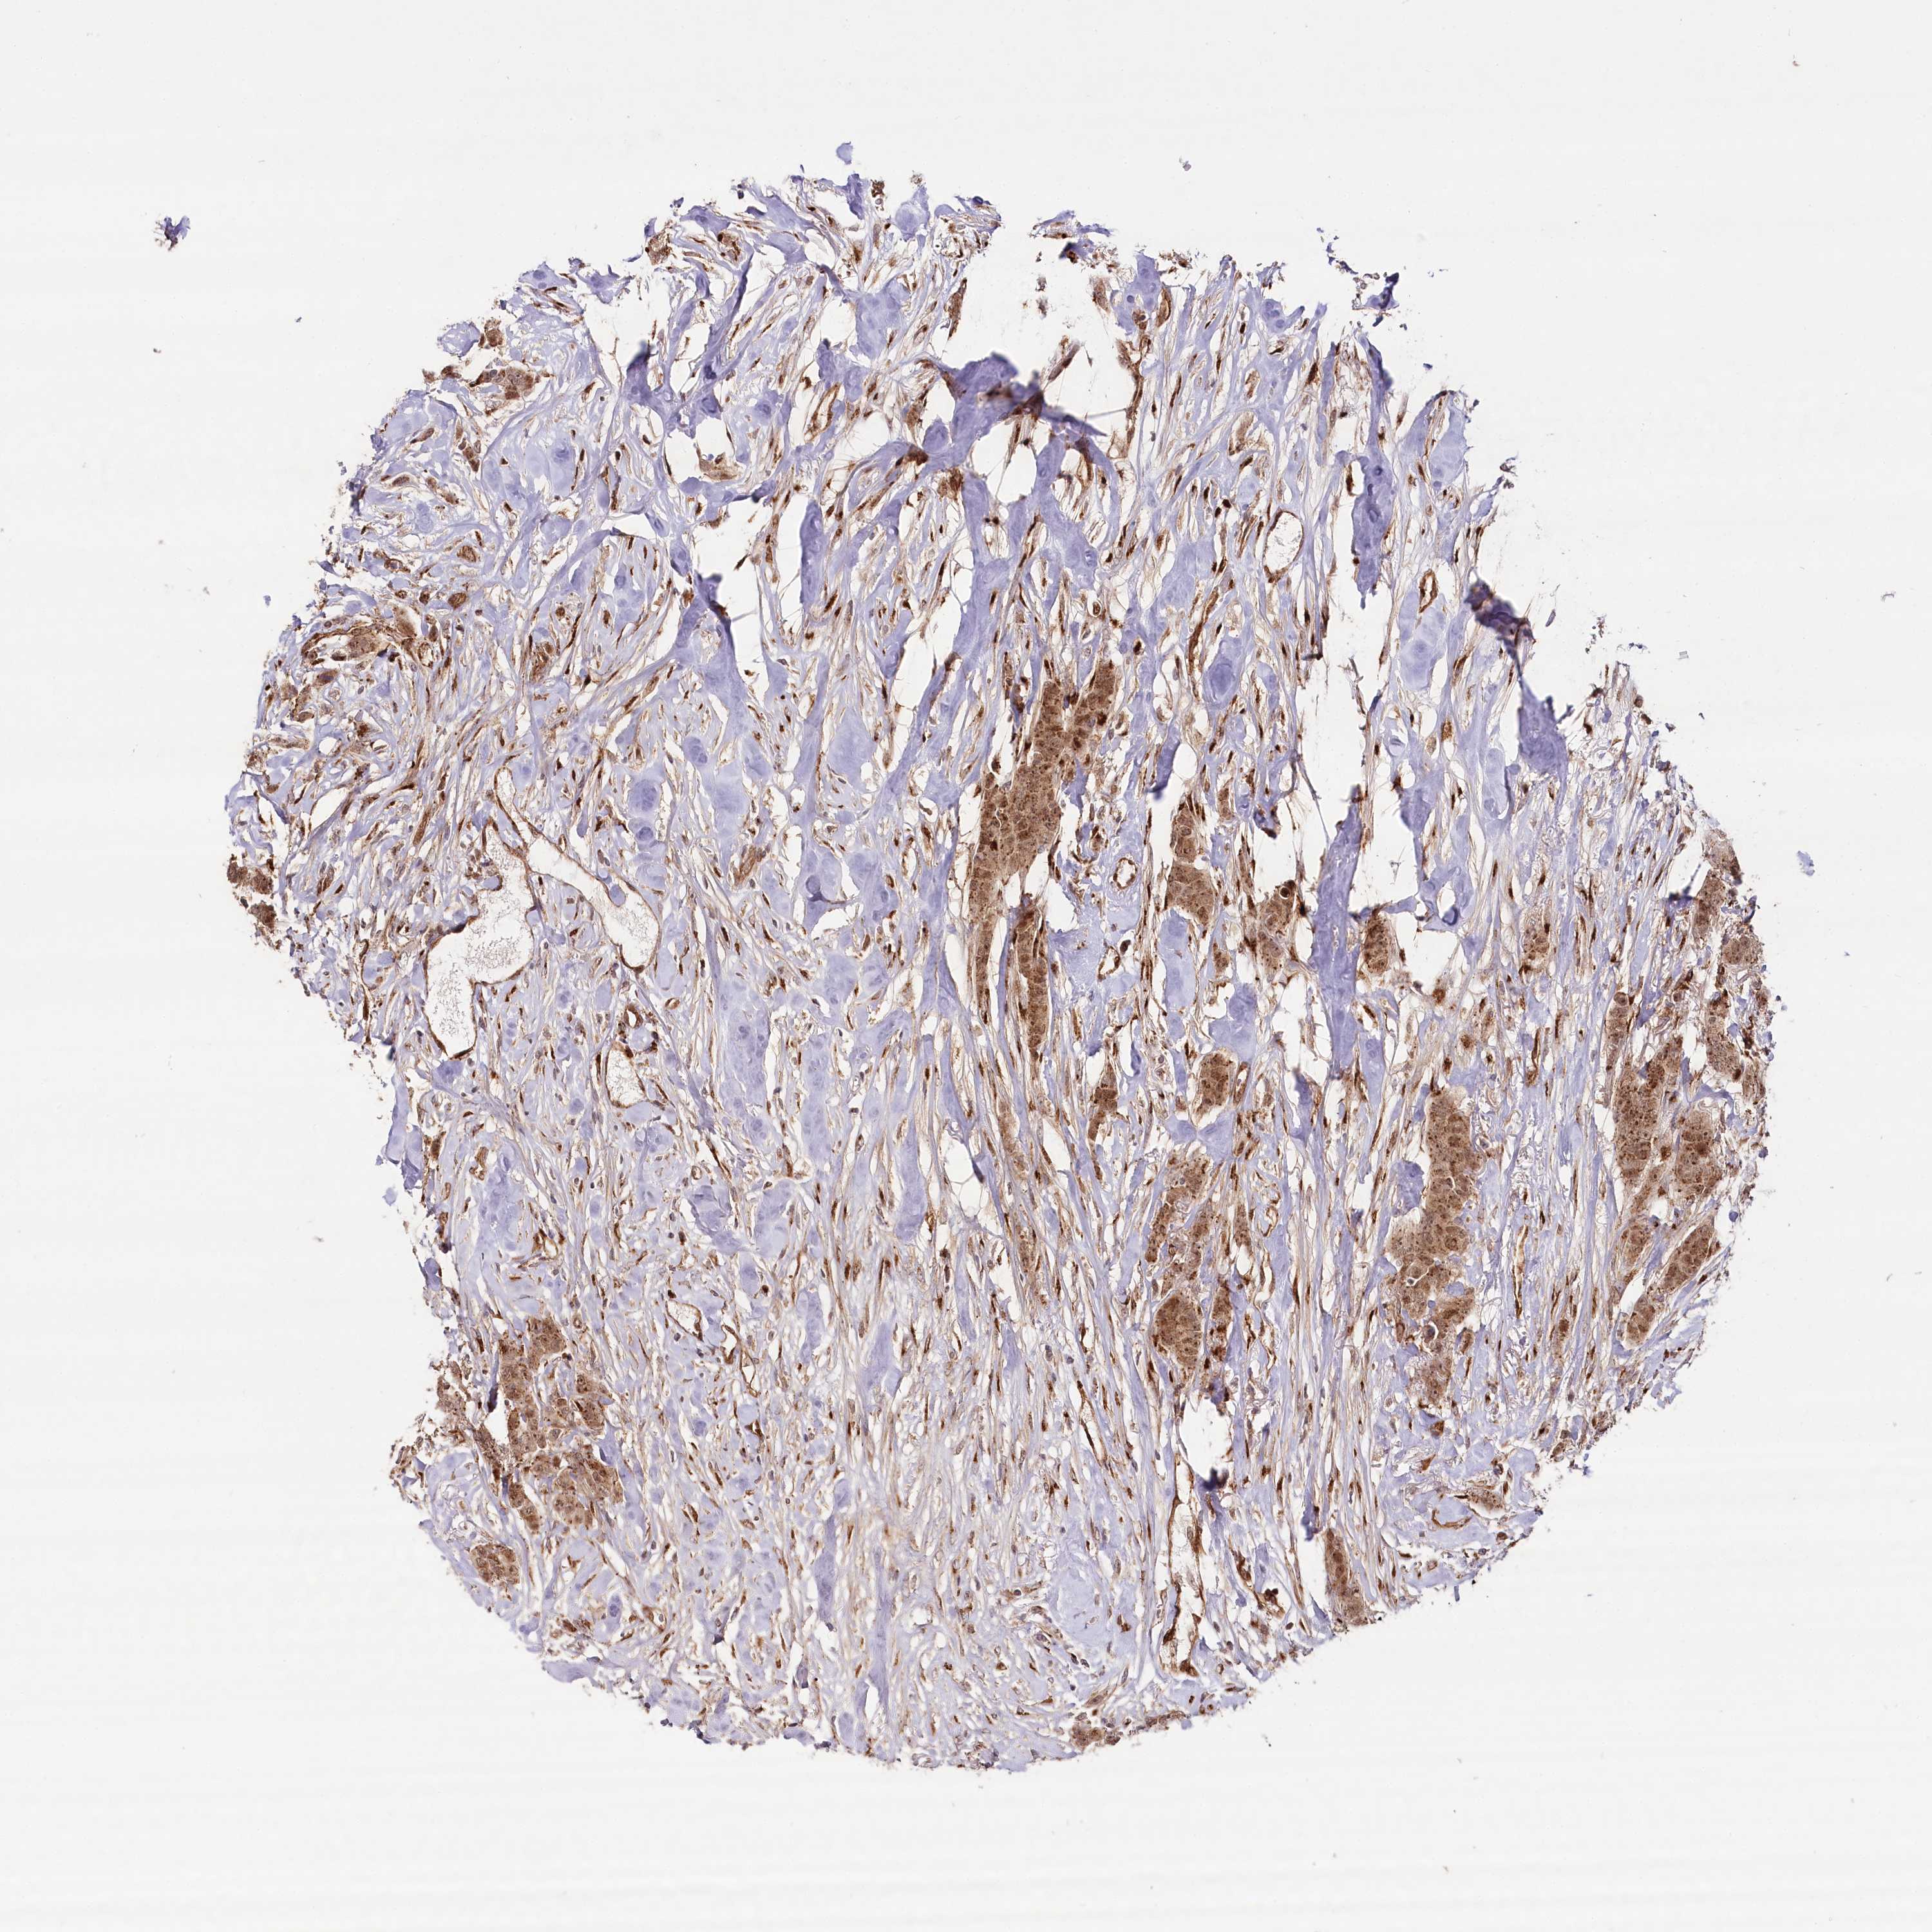

BRCA TCGA BRCA VALIDATION PROTEIN EXPRESSION

ANTIBODIES

AND

VALIDATION